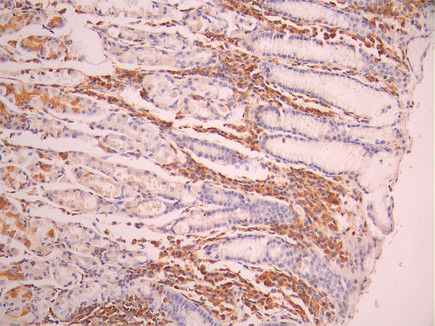

• IHC image of CSB-RA185006A0HU diluted at 1:100 and staining in paraffin-embedded human stomach tissue performed on a Leica BondTM system. After dewaxing and hydration, antigen retrieval was mediated by high pressure in a citrate buffer (pH 6.0). Section was blocked with 10% normal goat serum 30min at RT. Then primary antibody (1% BSA) was incubated at 4°C overnight. The primary is detected by a Goat anti-rabbit polymer IgG labeled by HRP and visualized using 0.05% DAB.